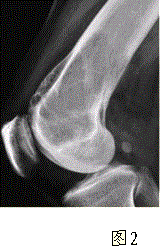

问题 患者女,35岁,左膝关节隐痛1年余,近1周加重,活动后明显疼痛。查体:左股骨下端外侧肿胀,压痛。行左膝关节正侧位CR,并行左膝关节CT扫描,见下图。 对本病例,应首先考虑的诊断是

选项 A.动脉瘤样骨囊肿 B.骨囊肿 C.成软骨细胞瘤 D.骨结核 E.骨巨细胞瘤 F.非骨化性纤维瘤

答案 E